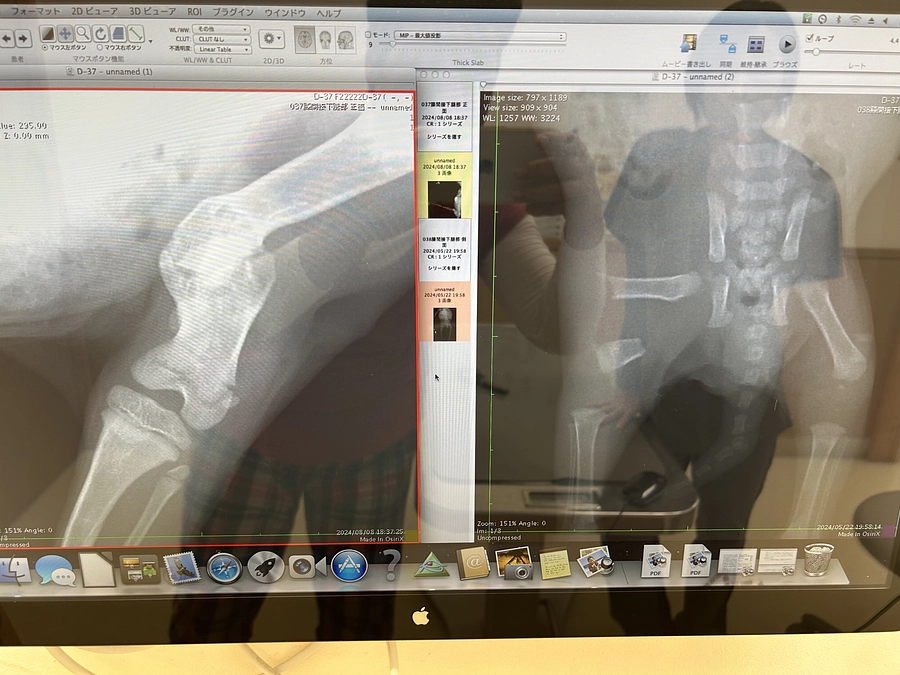

5月に膀胱の中を綺麗にして頂く手術をしてもらいましたが

抗生剤にも抗体できてしまって💦

感染症との闘いが続いております。。。

新しい抗生剤も効き始めて膀胱洗浄を続けながらの通院🏥

しかしその抗生剤の効きを上回るくらいの感染症でこないだから

またかなりの出血🩸で

ご飯も食べなくなってきて。。。

昨日も綺麗に膀胱洗浄して頂きました❣️

壊死した粘膜なのか?

大きい固まりが2つでてくれ

これが出て楽になりスッキリしてくれたらいいのにな。。。

注射が効いてくれたのか?

今朝はご飯も少し食べてくれました🐱